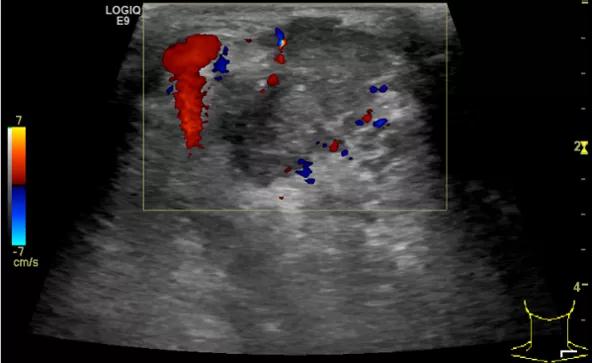

第二例是食管癌患者,术后半年余锁骨上固定淋巴结可触及肿大,疼痛非常明显,系统治疗后无缓解,患者希望通过局部处理缓解症状。造影显示强化信号明显,结节部分区域坏死,故主要针对强化区域从后向前的逐层的消融,皮下进行液体隔离减少烫伤。热消融后影像显示血流增强消失,弹性、硬度增高,一个月后复查显示充盈缺损,完全消融,疗效远超预期。

(病例2图例)